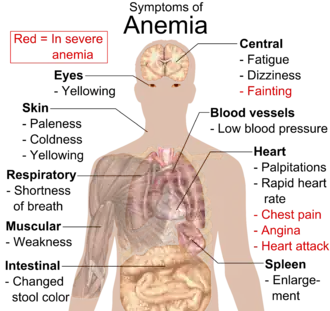

When anemia comes on slowly, the symptoms are often vague, such as tiredness, weakness, shortness of breath, headaches, and a reduced ability to exercise.[1] When anemia is acute, symptoms may include confusion, feeling like one is going to pass out, loss of consciousness, and increased thirst.[1] Anemia must be significant before a person becomes noticeably pale.[1] Additional symptoms may occur depending on the underlying cause.[1] Anemia can be temporary or long-term and can range from mild to severe.[6]

A person with anemia may not have any symptoms, depending on the underlying cause, and no symptoms may be noticed, as the anemia is initially mild, and then the symptoms become worse as the anemia worsens. A patient with anemia may report feeling tired, weak, decreased ability to concentrate, and sometimes shortness of breath on exertion.[21] These symptoms are unspecific and none of the symptoms alone or in combination show a good predictive value for the presence of anemia in non-clinical patients.[22]

Symptoms of anemia can come on quickly or slowly.[23] Early on there may be few or no symptoms.[23] If the anemia continues slowly (chronic), the body may adapt and compensate for this change. In this case, no symptoms may appear until the anemia becomes more severe.[20][24] Symptoms can include feeling tired, weak, dizziness, headaches, intolerance to physical exertion, shortness of breath, difficulty concentrating, irregular or rapid heartbeat, cold hands and feet, cold intolerance, pale or yellow skin, poor appetite, easy bruising and bleeding, and muscle weakness.[23]

Anemia that develops quickly, often, has more severe symptoms, including, feeling faint, chest pain, sweating, increased thirst, and confusion.[23][25][26][27] There may be also additional symptoms depending on the underlying cause.[1]

In more severe anemia, the body may compensate for the lack of oxygen-carrying capability of the blood by increasing cardiac output. The person may have symptoms related to this, such as palpitations, angina (if pre-existing heart disease is present), intermittent claudication of the legs, and symptoms of heart failure.[28]

On examination, the signs exhibited may include pallor (pale skin, mucosa, conjunctiva, and nail beds), but this is not a reliable sign.

Iron-deficiency anemia may give symptoms that can include spoon-shaped nails, restless legs syndrome, and pica (the medical condition indicates the desire for things that are not food, such as ice, dirt, etc.).[29] A blue coloration of the sclera may be noticed in some cases of iron-deficiency anemia.[30] Vitamin B12 deficiency anemia may result in decreased ability to think, memory loss, confusion, personality or mood changes, depression, difficulty walking, blurred vision, and irreversible nerve damage.[31][32] Other specific causes of anemia may have signs and/or complications such as, jaundice with the rapid break down of red blood cells as with hemolytic anemia, bone abnormalities with thalassemia major, or leg ulcers as seen in sickle cell disease.

In severe anemia, there may be signs of a hyperdynamic circulation: tachycardia (a fast heart rate), bounding pulse, flow murmurs, and cardiac ventricular hypertrophy (enlargement). There may be signs of heart failure. Pica, the consumption of non-food items such as ice, paper, wax, grass, hair or dirt, may be a symptom of iron deficiency;[29] although it occurs often in those who have normal levels of hemoglobin. Chronic anemia may result in behavioral disturbances in children as a direct result of impaired neurological development in infants, and reduced academic performance in children of school age. Restless legs syndrome is more common in people with iron-deficiency anemia than in the general population.[33]